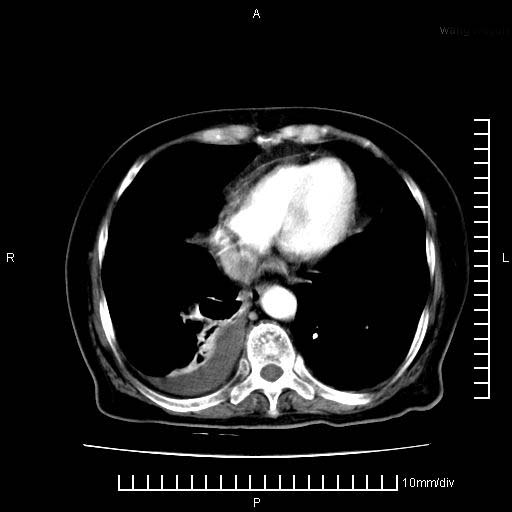

上腹疼痛月余,外院核磁诊断胰腺癌。现临床示右下腹可明显触及包块,可片子上怎么没有看到?

1.胰腺颈体部癌。

胰腺体部癌累及周围器官,腹膜、粘连

1。胰腺ca伴腹膜腔转移

2。肝左叶低密度灶,考虑转移可能

胰腺结构模糊,胰尾部见囊性包块,周围脂肪密度增高,左肾前筋膜增厚,胸水、腹水。不符合胰腺ca伴腹膜腔转移。考虑胰腺炎伴假性囊肿形成、胸腹腔积液。

1、考虑胰腺癌伴腹膜腔转移,胸腹水。

1)考虑胰腺癌并胰腺假性囊肿形成。2)肝内低密度灶,不排除转移。3)右肾盂积水。4)腹水。5)右侧胸腔积液并右肺下叶部分膨胀不全。

考虑胰腺ca伴腹膜腔转移、肝左叶转移、右肾积水。右胸腔积液。